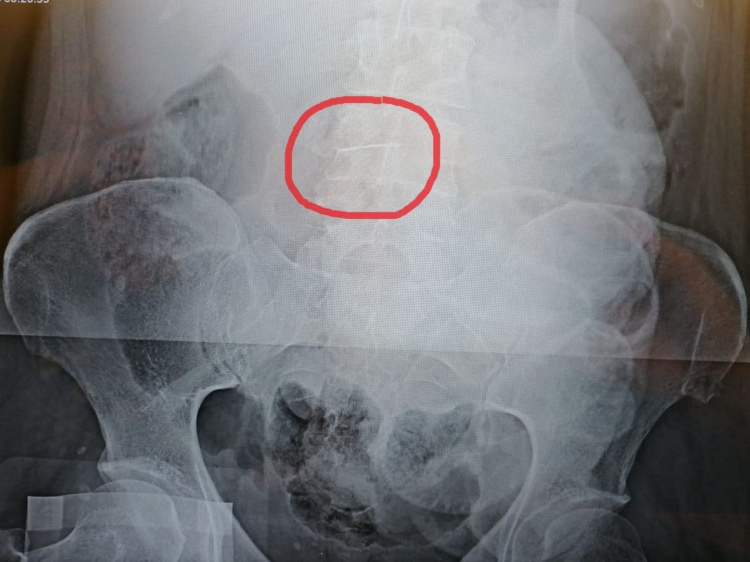

Как сообщили Волжский.ру в комитете здравоохранения, женщину привезли на скорой в областную клиническую больницу № 3 с подозрением на желудочно-кишечное кровотечение. По итогам обследования диагноз не подтвердился, но благодаря обзорной рентгенографии медики обнаружили в брюшной полости иглу, которая представляла смертельную опасность. Ко всему прочему, у пациентки диагностировали правостороннюю пневмонию, что утяжеляло состояние и прогноз операции. Но хирурги решили незамедлительно оперировать, ведь игла в любой момент могла начать движение и повредить органы.

Под рентгеновским контролем врачи извлекли иглу длинной 5 см, и в настоящее время пациентка идет на поправку. Кстати, после операции волгоградка вспомнила, как предмет мог попасть в тело: приблизительно в 2004 году она работала на швейной фабрике и могла получить случайную травму. Игла сначала попала в брюшную стенку, затем мигрировала в брюшную полость и застряла в сальнике.